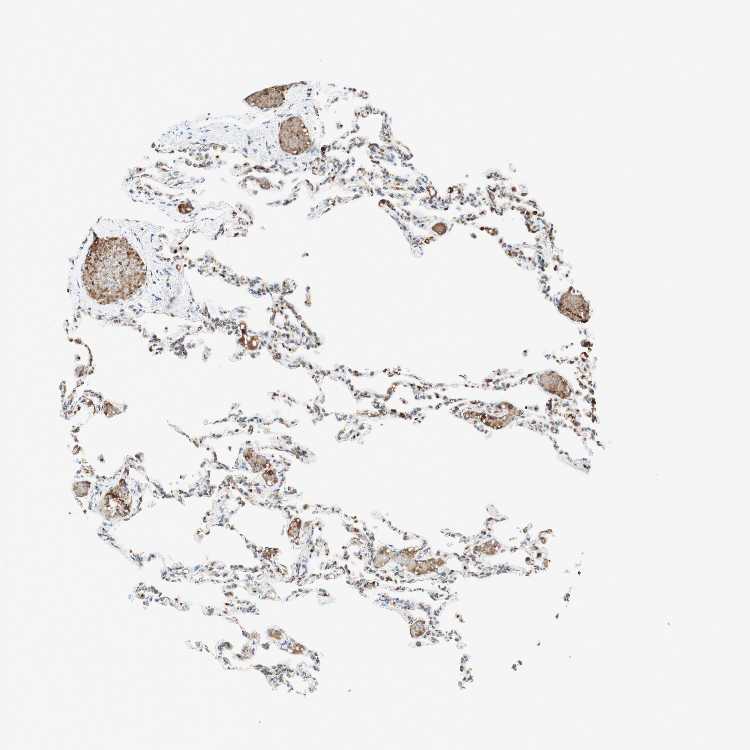

LUNG - Antibody stainingi

Antibody staining in the annotated cell types in the current human tissue is reported as not detected, low, medium, or high, based on conventional immunohistochemistry profiling in selected tissues. This score is based on the combination of the staining intensity and fraction of stained cells.

Each image is clickable and will lead to virtual microscopy that enables deeper exploration of all samples and also displays staining intensity scores, fraction scores and subcellular localization as well as patient and tissue information for each sample.

Antibody HPA011008Antibody HPA011555

Alveolar cells High-

Alveolar cells type I -High

Alveolar cells type II -High

Endothelial cells -Not detected

Macrophages HighHigh